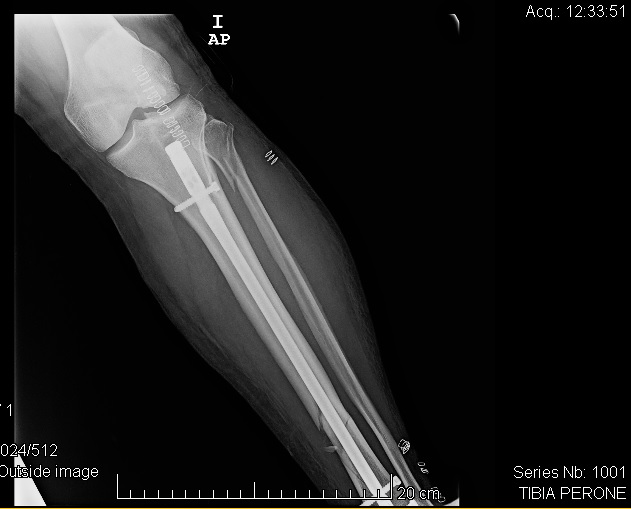

Tras las primeras radiografías se confirman las sospechas, rotura de tibia y peroné.

Expresar también mi agradecimiento a la profesionalidad, celeridad y buen trato recibido del personal de Urgencias del Hospital de La Línea y como durante varias horas, los vi trabajar a destajo haciendo frente al montón de urgencias que pasaron por allí en ese día, así como al personal de Urgencias y Traumatología de la Clínica de San Rafael de Cádiz, lugar donde fuí intervenido y donde me implantaron un clavo y cuatro tornillos que con la magia del hechicero, han recompuesto mi pierna con expectativas más que halagueñas de recuperación.